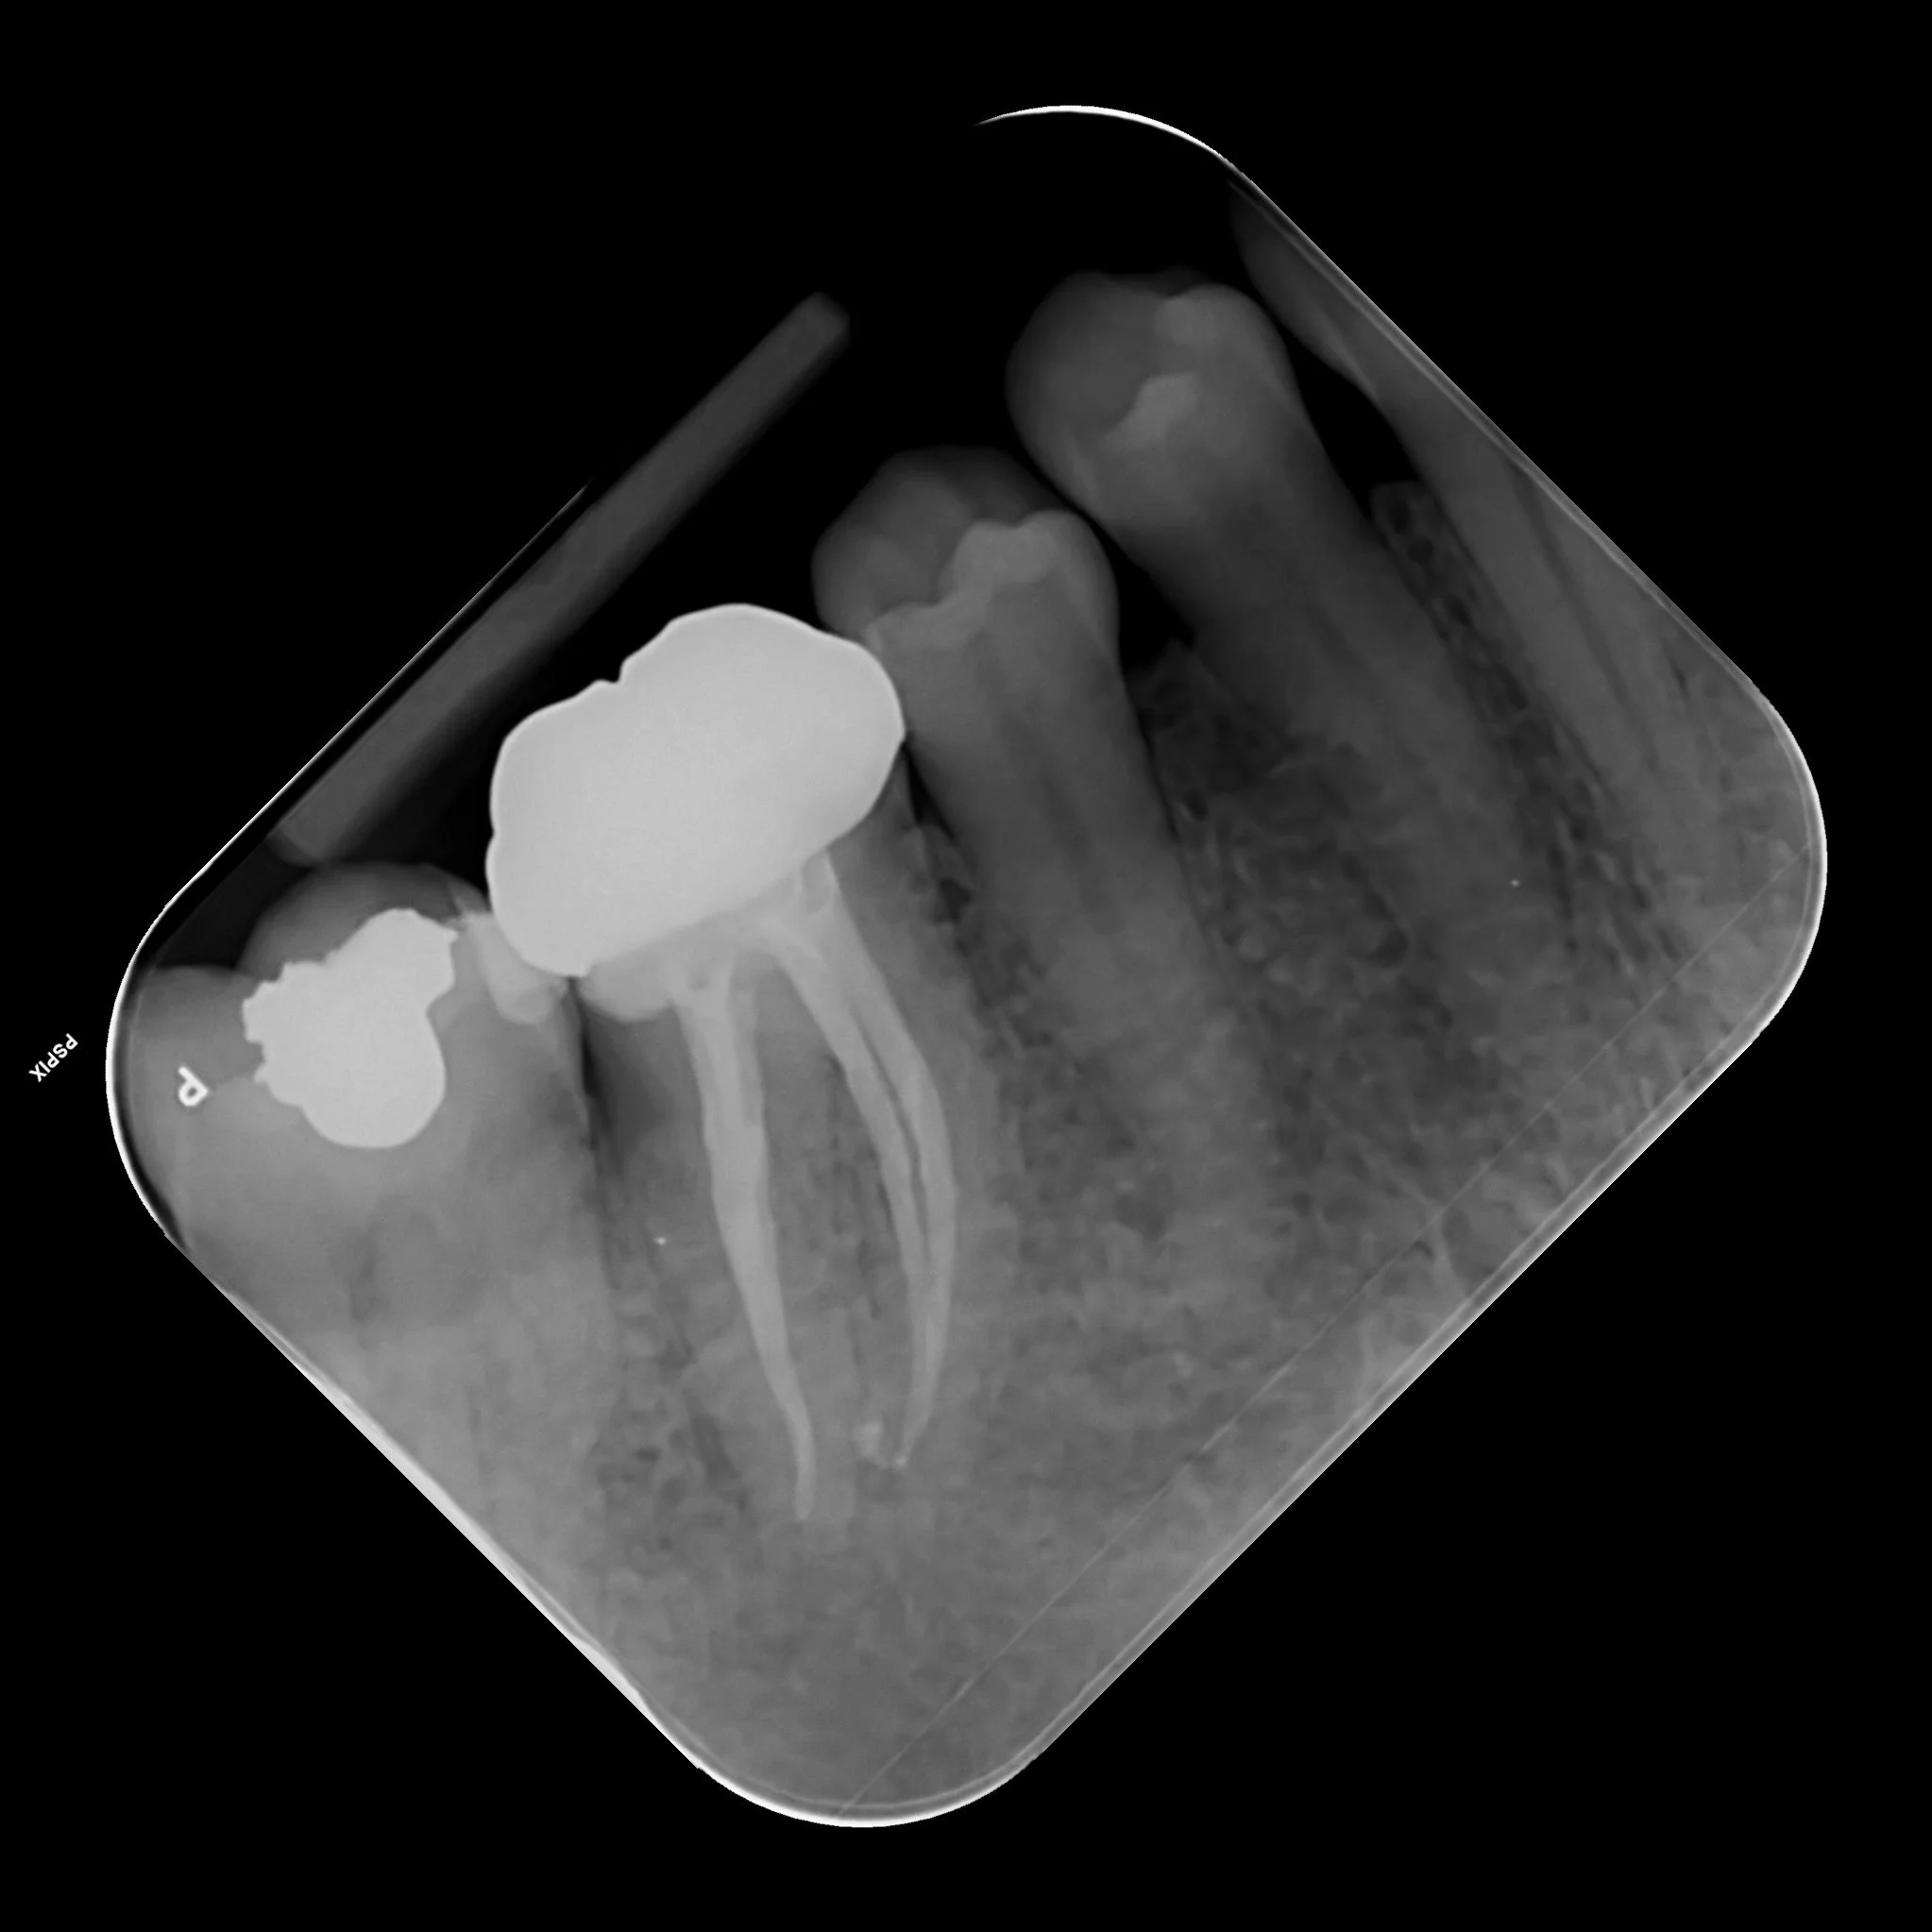

Patient presented with a large infection beneath a lower molar. Emergency treatment provided to get the patient out of pain. Second appointment to provide root canal therapy. Crown fitted to protect the tooth. Review x-ray shows favourable healing.